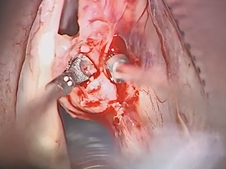

Transcervical Exploration of Parapharynx for Deep Lobe Parotid Pleomorphic Adenoma

Uvulopalatopharyngoplasty (UPPP)- Lateral Expansion Pharyngoplasty Variant with Uvulopalatal Flap